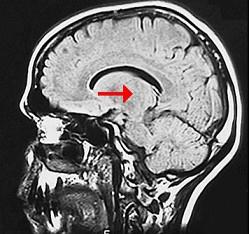

问题 如图箭头所示为大脑哪个部位 ( )

选项 A、松果体 B、中脑导水管 C、豆状核 D、尾状核 E、丘脑 一、单项选择题

答案 E